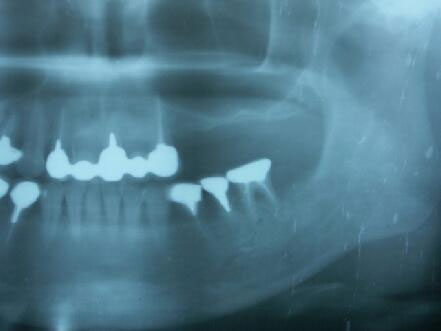

術前エックス線写真と口腔内写真

この方も上顎洞の下縁の骨が1〜3ミリ程度しかなくソケットリフトでは不可能なのでサイナスリ フトの選択となる

インプラント体(フィクスチャー)の周りに骨が出来始めている

4ヵ月後のエックス線写真

この症例も十分咬合に耐える、しっかりした骨が形成されています。